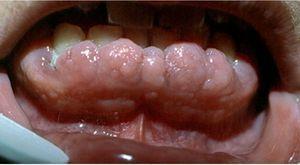

Hiperplasia gingival. No es propiamente una tumoración, pero puede llegar casi a ocultar los dientes (fig. 8). Presenta un aumento de las fibras colágenas y puede ocurrir sin una causa conocida o inducida por medicamentos, especialmente antiepilépticos (fenitoína) y ciclosporina, pero también verapamilo, nifedipino, diltiazem y otros muchos. Conviene diferenciarla también de la fibromatosis gingival hereditaria, los infiltrados en el curso de una leucemia y la hiperplasia gingival por falta de cuidados en la zona.

Figura 8. Hiperplasia gingival por medicamentos que debe distinguirse de la fibromatosis gingival hereditaria.